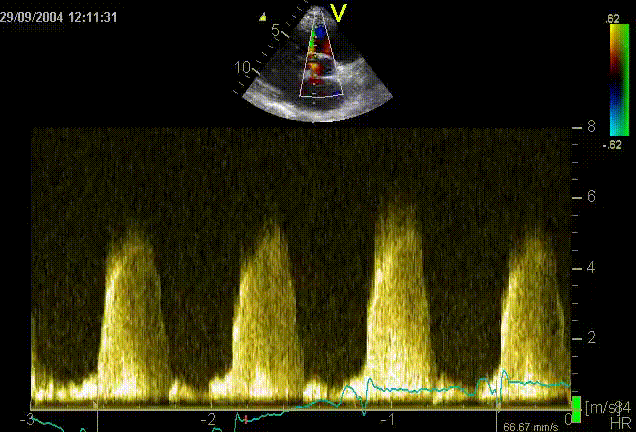

Case 45